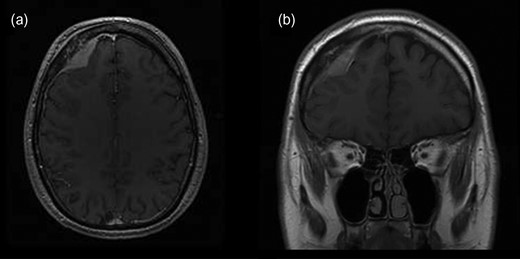

A 34-year-old male patient was presented with a 2-month history of intermittent headaches in the right frontal region. No other significant neurological deficits were found. Initial magnetic resonance imaging (MRI) revealed mass in the right frontal part of the skull (Fig. 1). The mass was attached to dura mater and it was mildly compressing the middle frontal gyrus beneath. Also, signs of intraosseal propagation were present. Patient underwent right side frontal craniectomy. Bone attached to the tumor was extracted. Duroplasty and cranioplasty were performed. Surgery went without complications. Postoperative computerized tomography (CT) was satisfying. Tissue samples from multiple sites of tumor connected to dura with surrounding bone were taken intraoperatively and underwent histopathological analysis. Tumor consists of large cells with pleomorphic nuclei and prominent nucleoli, with pathological mitotic figures. Tumorous tissue shows immunohistological reactivity for CD45 LCA, CD20, CD79a, CD10, BCL6 and PAX5. They were partly positive for BCL2 and CD30 and negative for CD3 and CD21. C-myc shows positivity in 36% of tumor cells. Proliferation index Ki67 is diffusely 75% (Fig. 2). According to WHO classification it corresponds to diffuse large B-cell lymphoma. Afterwards, extended diagnostics were performed. Bone marrow biopsy showed an abnormality in the percentage of non-segmented neutrophils of 17%. Other results showed medium–high erythropoiesis with normal cell ratios but without findings of malignant alteration or infiltration. A cylindrical sample showed no morphological nor immunohistochemical (CD20, PAX5, Ki67 and CD3) evidence of malignant infiltration. Lumbar puncture was also performed and cerebrospinal fluid (CSF) samples showed no positivity to malignant cells. Afterwards, full body CT was performed, followed by ultrasound including thyroid and salivary glands. Also, MRI of brain and spinal cord was done. All conducted imaging methods revealed normal anatomical and structural features without traces of lymph node enlargement or flee fluid throughout the body. A hematologist was consulted and methotrexate or R-CHOP therapy was recommended.

Initial brain MRI showing extra-axial mass in the right frontal part of anterior cranial fossa in (a) transverse and (b) coronal plain.